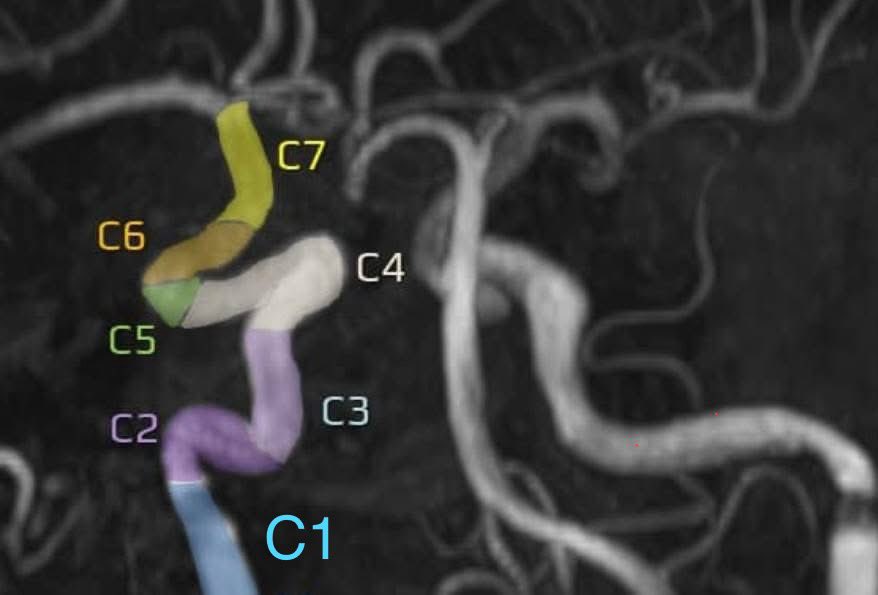

Persistent Trigeminal Artery (<1% prevalence) – A rare embryonic remnant that connects the ICA with the basilar artery It may serve as a collateral pathway but can be associated with a variety of vascular lesions

Persistent Trigeminal Artery (&lt;1% prevalence) – A rare embryonic remnant that connects the ICA with the basilar artery

It may serve as a collateral pathway but can be associated with a variety of vascular lesions